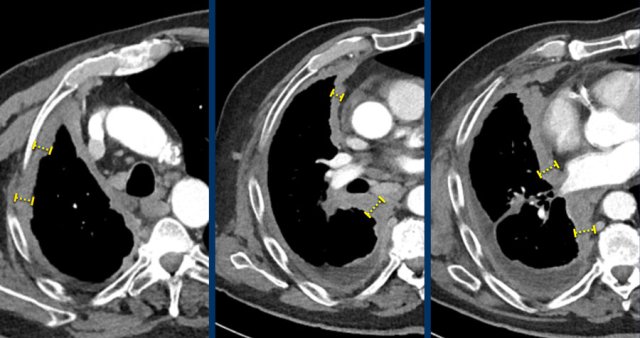

Measurements of the tumour thickness perpendicular to the chest wall or mediastinum in two positions at three different levels. Measurements of the tumour thickness perpendicular to the chest wall or mediastinum in two positions at three different levels.

Mesothelioma

An exception to measuring the longest diameter is in patients with malignant pleural mesothelioma.

The non-spherical growth pattern in this disease makes reproducible long axis measurements difficult.

Therefore not the longest diameter, but the tumour thickness perpendicular to the chest wall is used.

This measurement has a good correlation with outcome.

CT images in a 63-year-old male with malignant pleural mesothelioma.

Measurements according to the modified RECIST 1.1 for malignant pleural mesothelioma with measurement of the tumour thickness perpendicular to the chest wall or mediastinum in two positions at three different levels, preferably in the upper thorax.